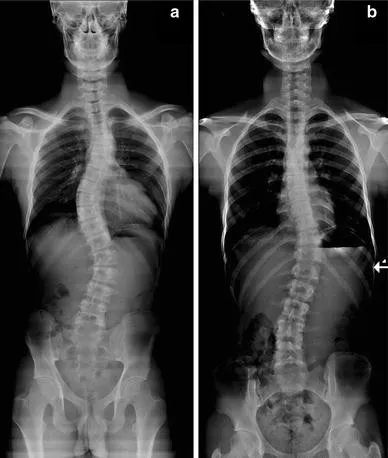

---Denver Gonstead is distinguished by its use of the Gonstead System, a highly specific and thorough method of chiropractic care. This approach goes beyond generalized adjustments to provide precise, gentle, and effective treatments. By using a detailed analysis, including in-house x-rays, Dr. Shane can pinpoint the exact cause of a patient's issues and provide a targeted solution. This meticulous attention to detail is a hallmark of the clinic's services and is a key reason why it achieves such positive results.

- In-House X-Rays: The availability of on-site x-ray facilities allows for a detailed and accurate diagnosis, which is crucial for developing the most effective and safe treatment plan.

- Comprehensive Diagnostic Tools: In-house x-rays take the care to the "next level," providing an accurate foundation for treatment and ensuring safety and efficacy.